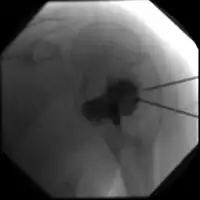

X-ray and CT scan show lytic expansion lesions with clear borders.[1] Expansion of cortex gives the lesion a balloon-like appearance. Larger lesions may appear septated.[10] MRI reveals fluid levels.[1] Bone scan shows outer radiotracer uptake, with a central dark area.[1]

ABC shoulder -

DSA: ABC of shoulder -